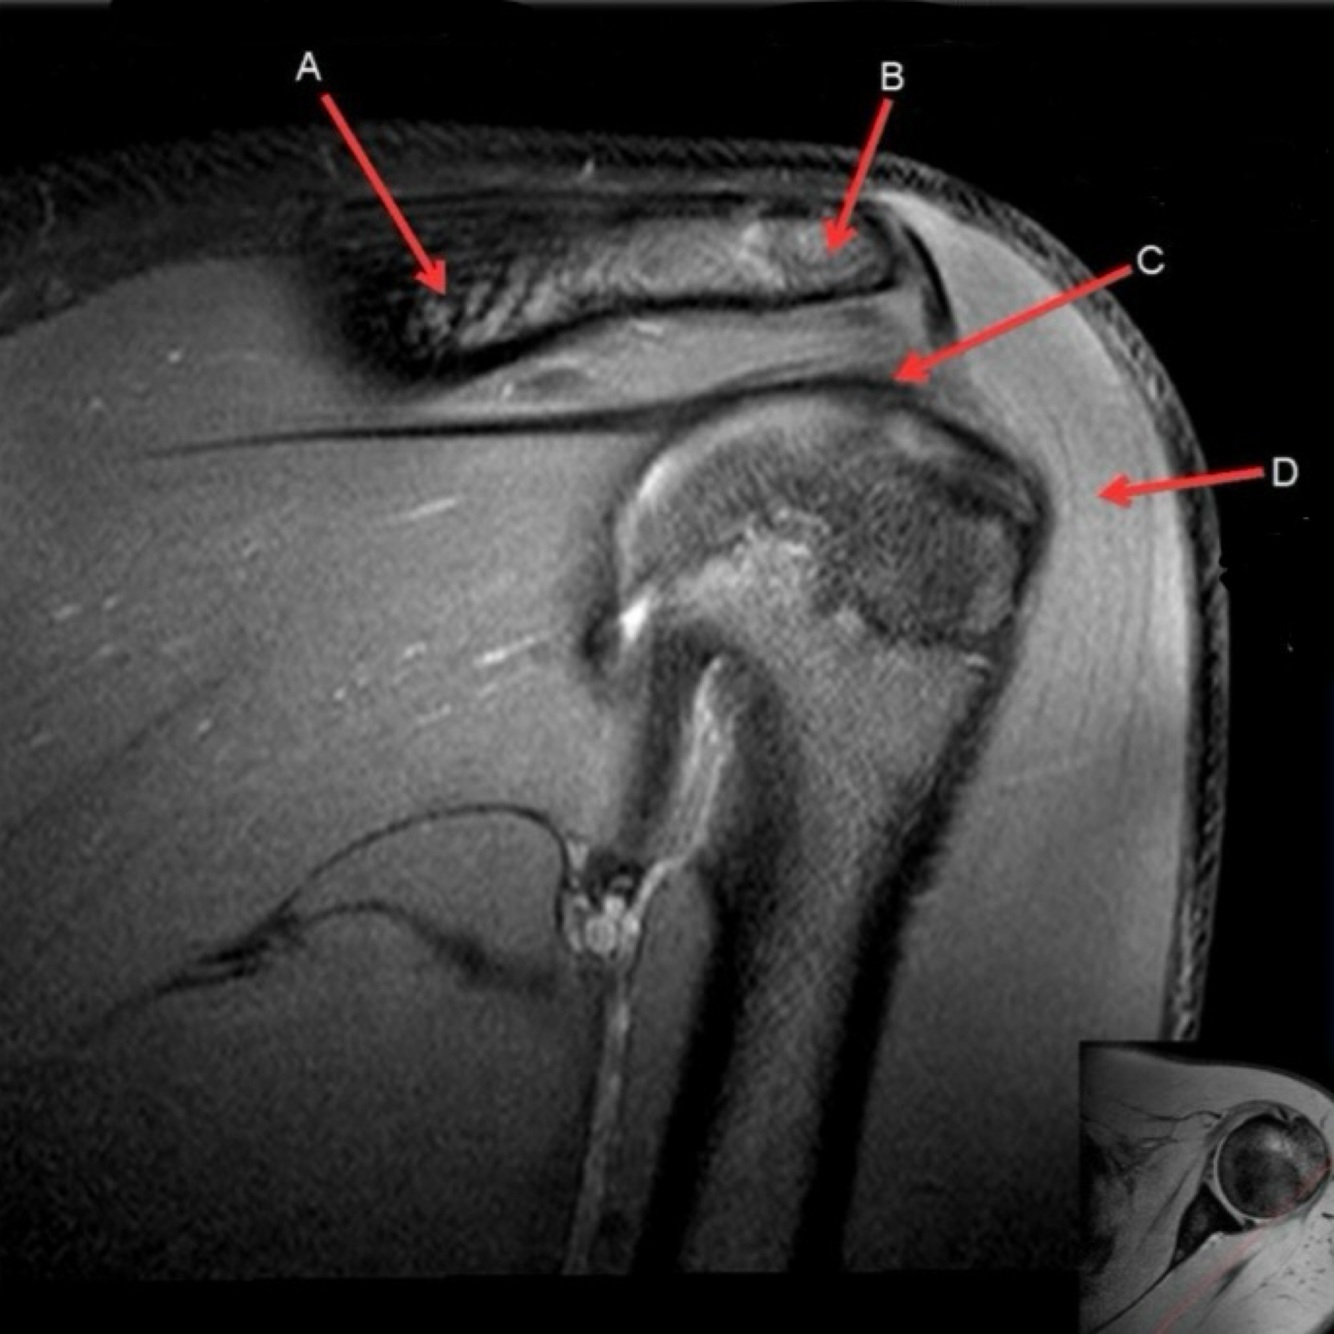

1

What is letter A?

SUPRASPINATUS TENDON

Q

A

17

What is letter C?

ACROMION

18

What is letter D?

DELTOID MUSCLE